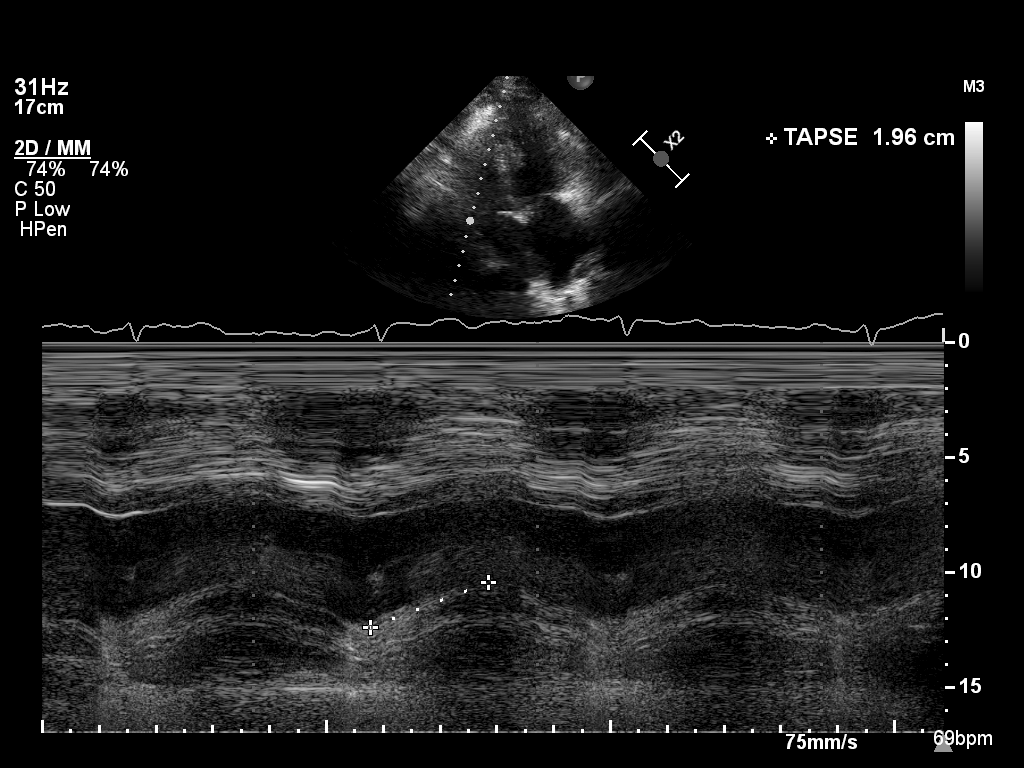

mmode-a4ch-rv mmode-a4ch-rv M-mode for measuring TAPSE

mmode-ivc mmode-ivc M-mode of the inferior vena cava